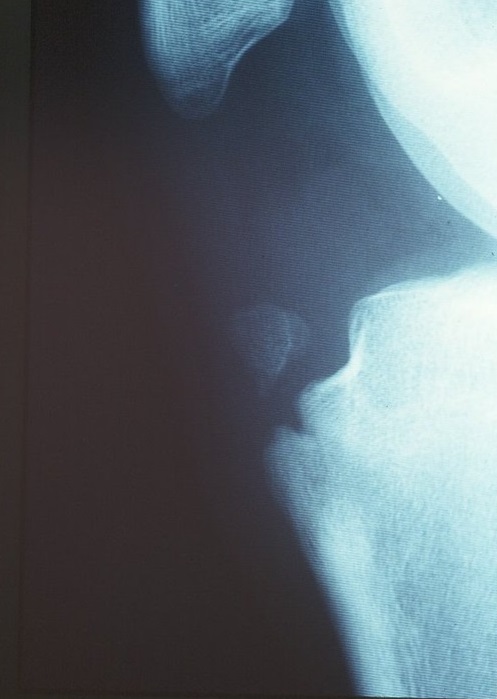

X-rays are the most helpful, which shows changes in the epiphyseal nuclei and free fragments localized to the tibial tuberosity (Photo 2), but they vary in size depending on the stage of disease. Magnetic resonance imaging (MRI) is even more useful in detecting thickening of the patellar tendon over the cartilage and surrounding inflammatory changes (Photo 3). Ultrasound can also show enlarged bones and tendons, as well as new blood vessels. (Photos 4 and 5)

Photo 2 X-ray